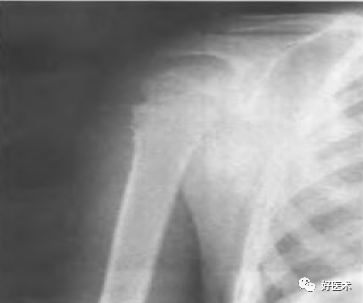

肱骨外科颈骨折 无移位型

外科颈骨折 外展型

外科颈骨折 内收型

外科颈骨折 伸展型

解剖颈骨折

大结节骨折

合并肩关节半脱位,大结节撕脱性骨折

合并肩关节脱位的大结节骨折

肩关节半脱位